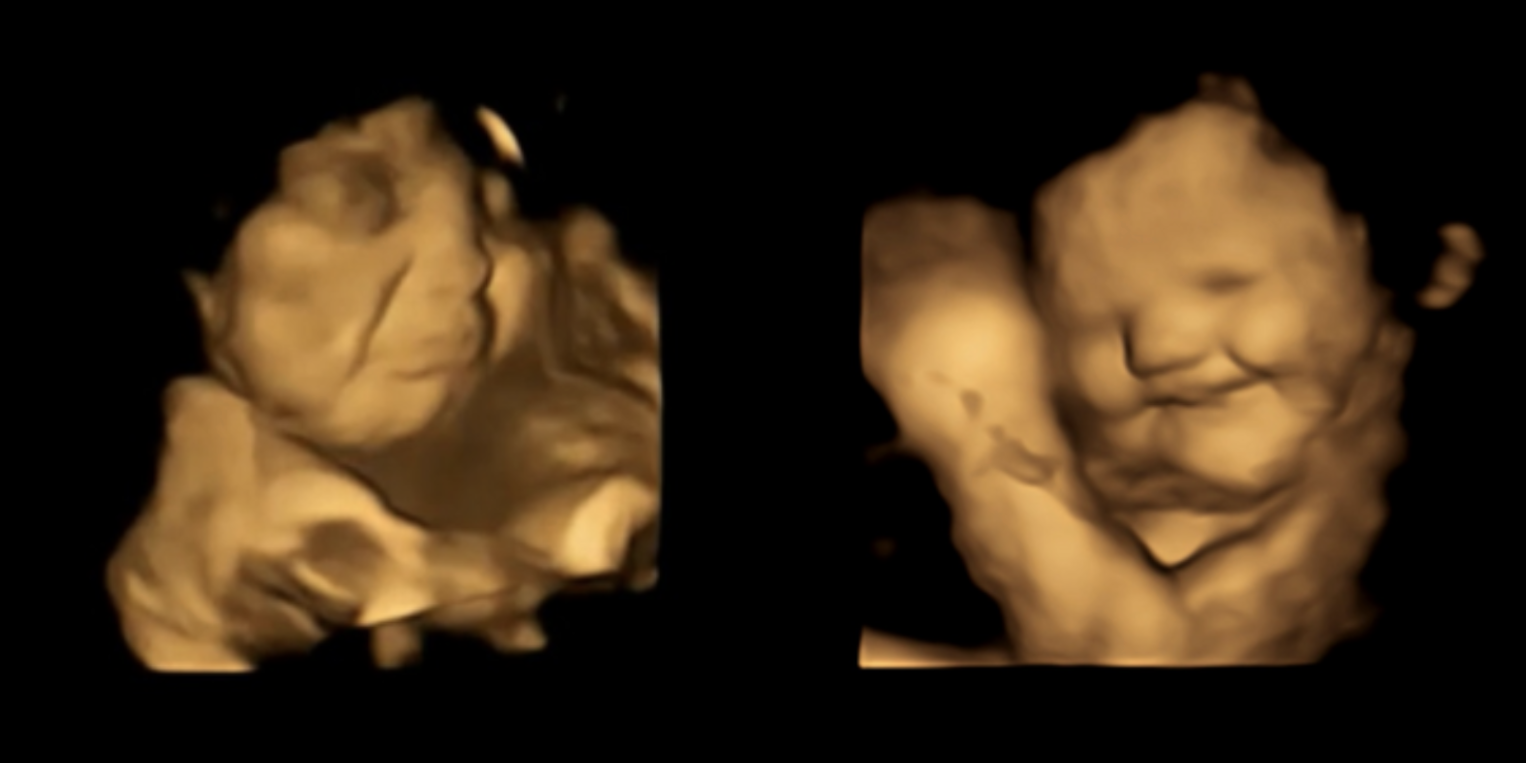

El sabor de la col rizada hace que los bebés no nacidos hagan una mueca, pero sonríen con las zanahorias, según un nuevo estudio de imagen

En un estudio realizado con un centenar de mujeres embarazadas del reino unido -publicado en línea en la revista psychological science-, los investigadores observaron...